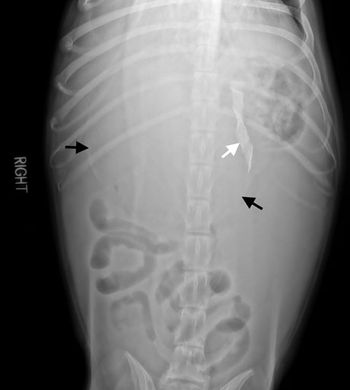

This case report describes the clinical signs and surgical treatment of an unusual hiatal hernia in a Chinese Shar-Pei.